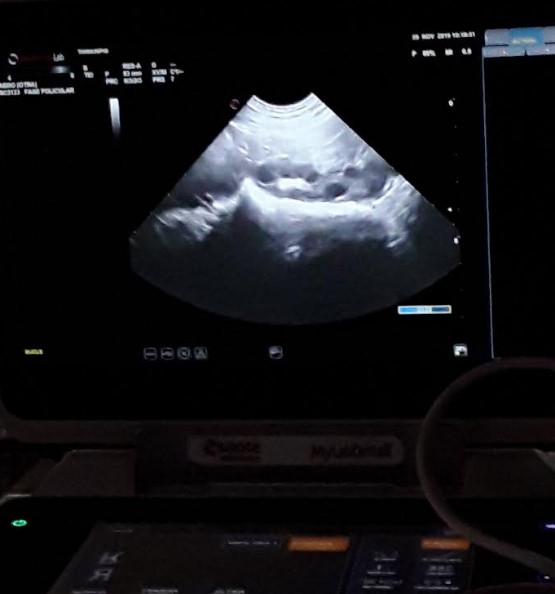

Figura 4. Nulípara en proestro, ovario con folículos.

Conociendo la dinámica folicular, se puede predecir el momento de ovulación. Folículos de 4mm ovularán en 40 horas, folículos de 5mm ovularán en 32-35 horas, folículos de 6mm ovularán en 24 horas y la ovulación está sucediendo cuando el folículo mide 8-9mm.

Al momento de realizar la ecografía a las hembras recién inseminadas, se observaron folículos de 5mm y otras que llevaban 24 horas post IA tenían folículos de 5,6mm (Figura 5). En ambos casos las inseminaciones se estaban anticipando, cubriendo a las cerdas varias horas antes de la ovulación, lo que provoca que la primera IA se esté desperdiciando. Se le explicó al personal que esas hembras que están inseminando los jueves, las pueden mover al viernes por la tarde o sábado en la mañana y con ello incrementar fertilidad.

Figura 5. Folículos preovulatorios de 5,6mm.